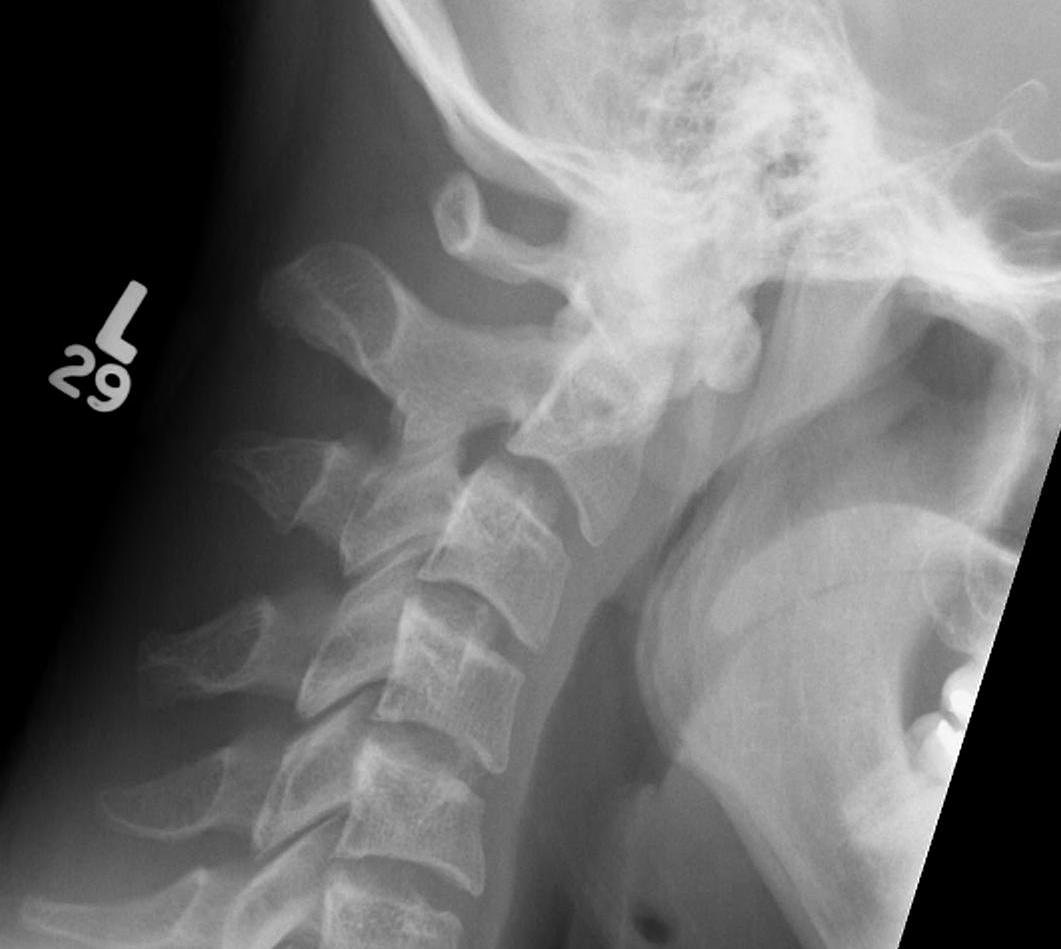

Jefferson Fracture Flexion Extension Views Stabe0001Jefferson Fracture Flexion Extension Views Stabe0002

Flexion and extension views demonstrating stable Jefferson fracture post halo treatment